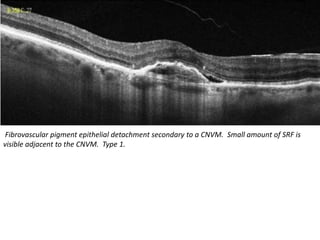

Fibrovascular pigment epithelial detachment secondary to a CNVM. Small amount of SRF is

visible adjacent to the CNVM. Type 1.